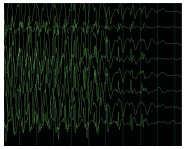

2.2 脑电监测资料本研究共纳入58例患者,其中男性35例,女性23例,在原发疾病组成中,颅脑外伤14例,脓毒症20例,心肺复苏术后17例,其他7例,APACHE Ⅱ评分(21.26±7.39),NSE水平(24.98±11.89)ng/ mL,S100β水平(0.46±0.67)μg/L。20例患者使用8导导联进行监测,38例患者使用16导导联进行监测,监测时间为(7.27±7.28) h,5例患者监测期间出现抽搐,51例患者的脑电监测存在异常,24例患者的脑电监测中存在三相波等特殊波形,其中三相波2例, 周期样放电7例,痫样波7例,爆发-抑制2例,43例患者出现不同程度的脑电节律减慢,部分波形见图 1-图 4,脑电监测异常的患者S100β水平较正常患者更高;见表 2,脑电监测的平均Young评分为(3.03±1.43),Synek评分为(2.51±1.68)。

| 脑梗死,脑电监测提示爆发-抑制波形 图 3 84岁男性 Figure 3 84-year-old male |

| 癫痫、CPR17 min,脑电监测提示痫性放电 图 4 33岁女性 Figure 4 33-year-old male |